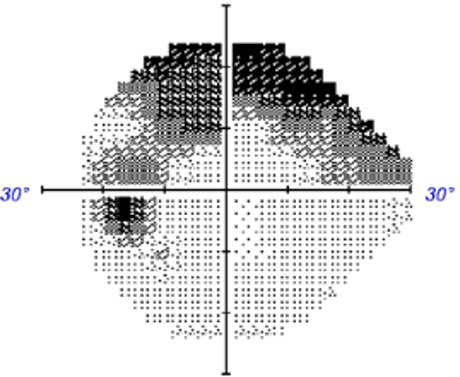

There are several visual field defects typically associated with glaucoma. They are typically described to be "retinal nerve fibre layer bundle" defects. It is important to realise however that these same defects may also be associated with other conditions so cannot be used in isolation to reach a diagnosis of glaucoma. The most common glaucomatous field defects are as follows:

1.Arcuate defect: Field loss extending from the blind spot to the nasal field with at least one point outside 15⁰ nasally and at least one abnormal point temporally

2. Nasal step: Field loss respecting the nasal horizontal midline with at least 1 abnormal point outside 15⁰. No more than 1 point may be on the temporal side.

3. Paracentral defect: : A small visual field abnormality not contiguous to the blind spot and within 15⁰ of fixation, obeying the horizontal midline.

4. Ring scotoma/peripheral constriction: Typically seen in advanced glaucoma and caused by the presence of both superior and an inferior arcuate defects.Rarely, the following defects may also be associated with glaucoma (although other causes are more likely):

Case 4: Peripheral field constriction

A 75 year old Caucasian male who reports good general health and a family history of glaucoma in his mother. This case will focus on his right eye. His intraocular pressure is 19mmHg in the context of average central corneal thickness (558µm).